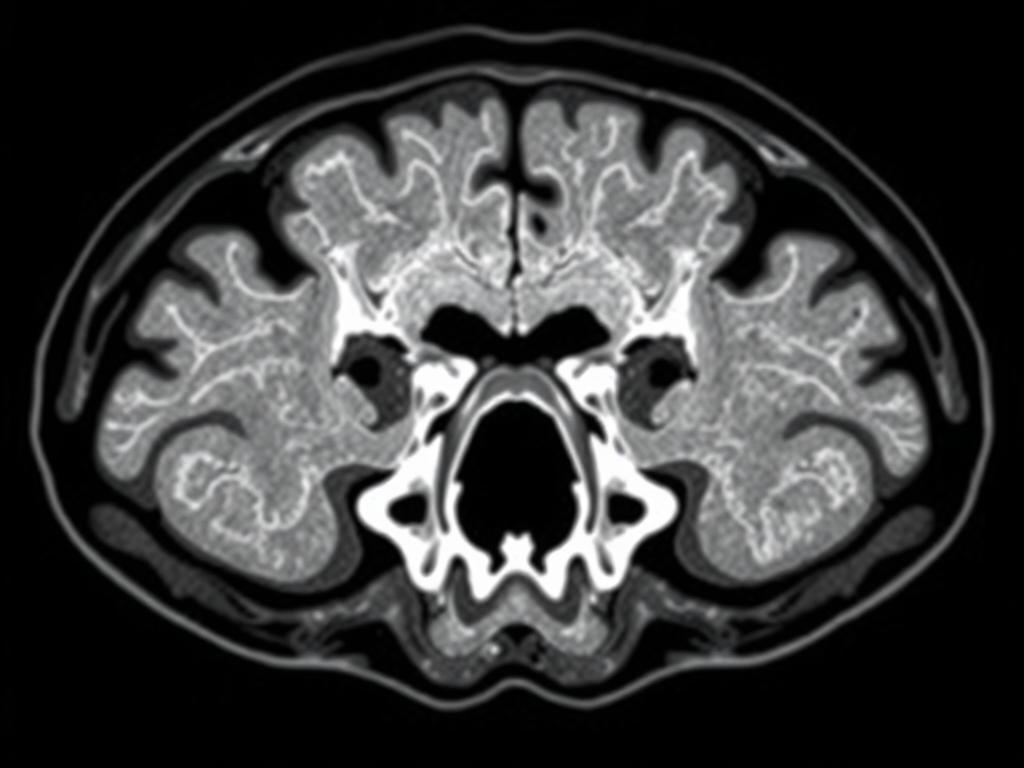

Компьютерная томография — это современный и очень точный метод диагностирования различных заболеваний. Особенно она незаменима, когда нужно рассмотреть сложно устроенные структуры черепа и уха. Височные кости имеют очень сложное строение и содержат важные элементы слухового анализатора и равновесия. Понимание того, как работает КТ височных костей и чего ждать от этого исследования, поможет снизить тревогу и получить максимум пользы от процедуры.

Из-за сложной анатомии области с масштабными костными структурами и тонкими воздушными полостями, обычные рентгеновские снимки не дают полноты картины. КТ позволяет получить детальные послойные изображения, что значительно облегчает диагностику и помогает разработать план лечения.